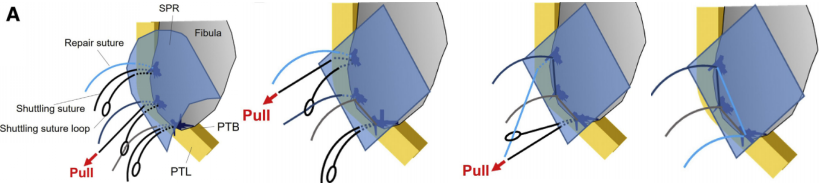

SPR撕脱开放手术锚钉修复

SPR撕脱关节镜手术锚钉修复

大部分急性损伤可以使用直接缝合修复,对慢性损伤则需根据患者的具体病理改变选择,如单纯的支持带结构损伤,可以直接缝合修复。如果直接修复不够稳定,需用其他组织加强。如果腓骨外踝窝较浅时,就需要使用加深手术。